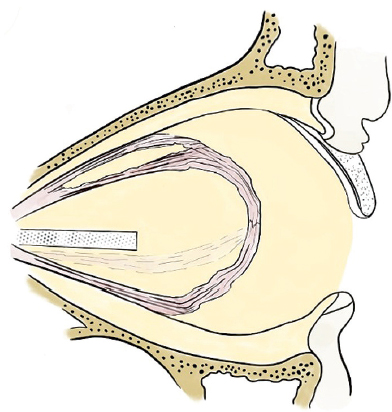

Fig. 11. Evisceration technique with removal of the cornea. Third stage: removal of the posterior pole of the sclera with neurectomy, installation of a spherical endoprosthesis

Рис. 11. Методика эвисцерации с удалением роговицы. Третий этап: удаление заднего полюса склеры с неврэктомией, установка сферического эндопротеза